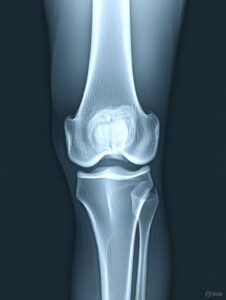

Özellikle yaşlandıkça diz eklemlerinde ve diğer eklemlerde sürtünmeyle beraber oluşan kireçlenme ya da tıbbi tabirle osteoartrit için pek çok tedavi yöntemi geliştirilmiştir. En iyi tedavi ilaç ya da diz ameliyatı gibi gözükse de eklemleri en iyi koruyacak ve osteoartrite en iyi gelecek tedavinin egzersiz olduğu belirtiliyor. Egzersiz pek reçete edilmese de eklemleri korumak için en …